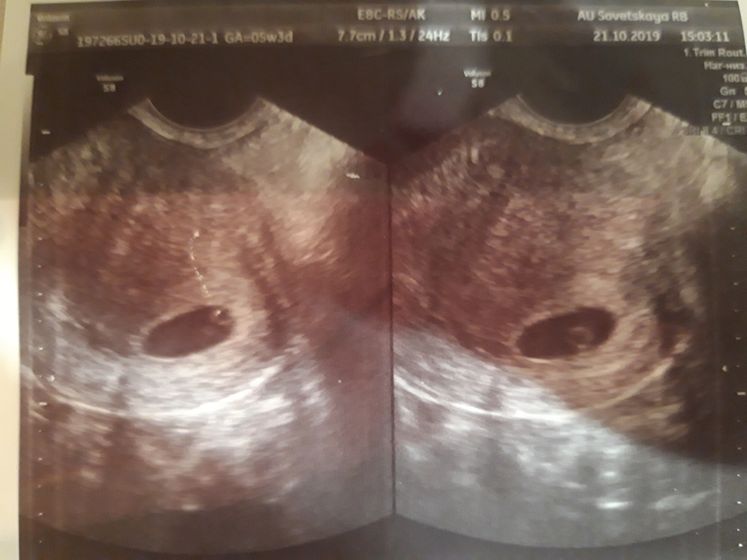

Всем доброго времени суток! Сегодня 21й день после переноса 1й бласточки 5дневочки и на УЗИ поставили ДВОЙНЮ под вопросом! Прибываем в приятном восторге) Контрольное УЗИ через неделю, еще неделя ожидания!!!

По УЗИ написали размеры ПЯ 18 мм и 1й жёлт.мешочек 3,4 мм, 2й 2,9 мм. Т.е они видят и размеры даже поставили четко. Ну более точного результата по контрольному узи ждем 28.10. О результатах напишу)))) ой как мы ждём ?

Ну вот и сходили на 2е УЗИ. Двойня подтвердилась))) один плод крупный КТР 6,6 мм ЧСС 170 жёлт.мешочек 2,5 мм, второй плод КТР 3мм и ЧСС 104, а вот тут большой желт.мешочек 5мм. Девочки, у кого как было с двойней, разница в 2 раза.